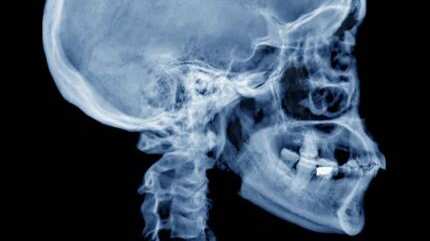

Según informó la citada casa de estudios, los expertos hallaron que esta protuberancia (que también fue llamada «pico» de hueso) se encuentra encima del cuello en la base del cráneo.

En términos más específicos, la «protuberancia occipital externa» es de un tamaño tan notorio que es fácilmente palpable al presionar dicha zona con los dedos.

El estudio determinó que al menos el 41% de los individuos analizados tenían este «pico» de hueso en la base del cráneo, teniendo en promedio un tamaño superior a los 20 milímetros. Incluso, el mayor era de 35,7 milímetros.